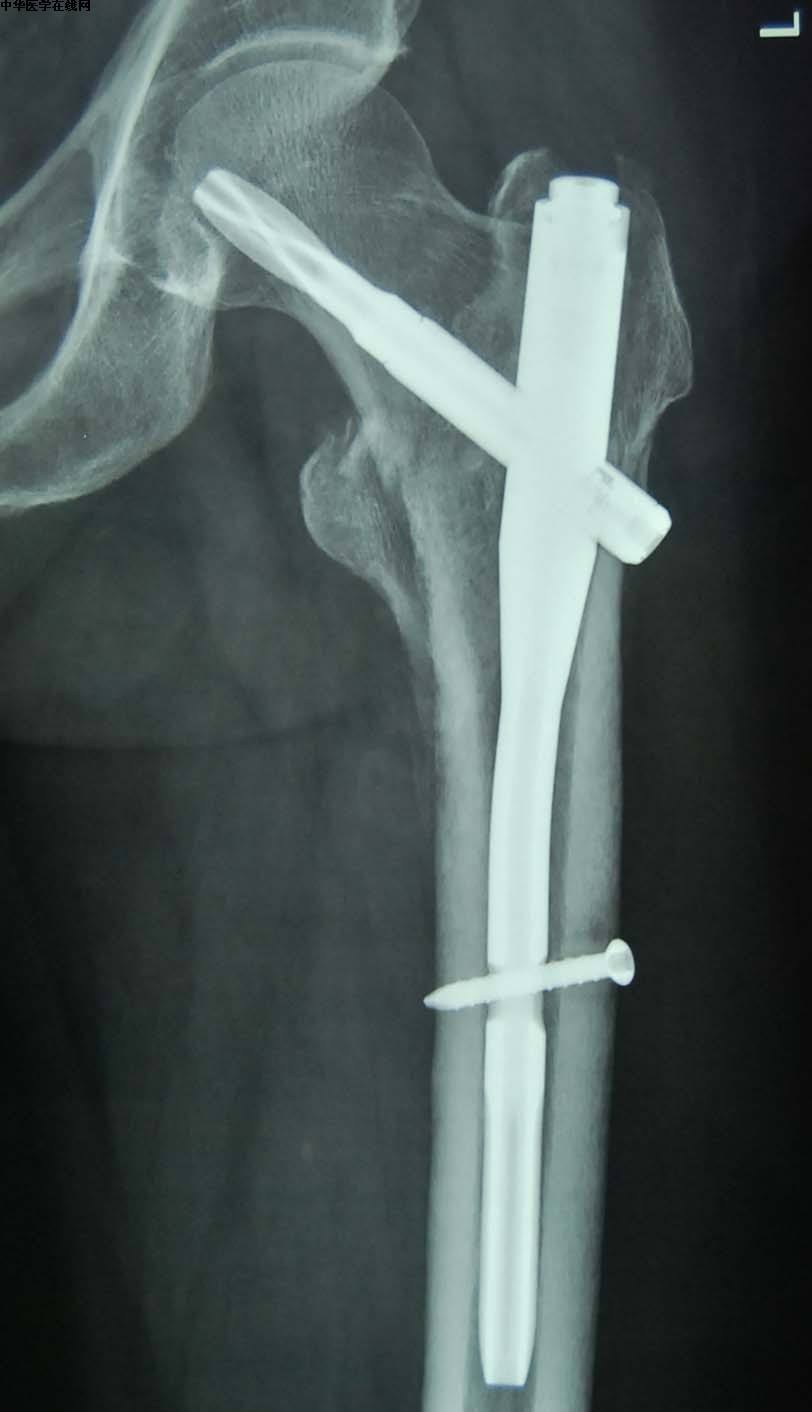

股骨粗隆间骨折微创治疗术后片